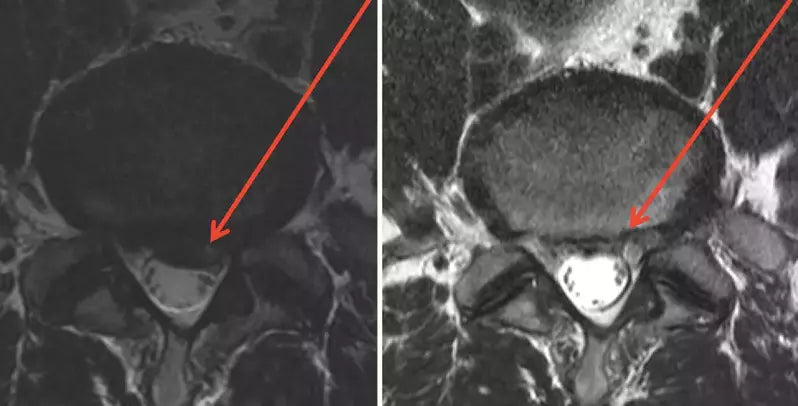

The comparison of the before and after MRIs are shown below. The herniation is depicted by the arrows.

The surgeon was surprised by this MRI finding and had to admit the success. The patient stated that he had no problems with tough military training. This case underscores the potential benefit of prolotherapy with a specific injury.